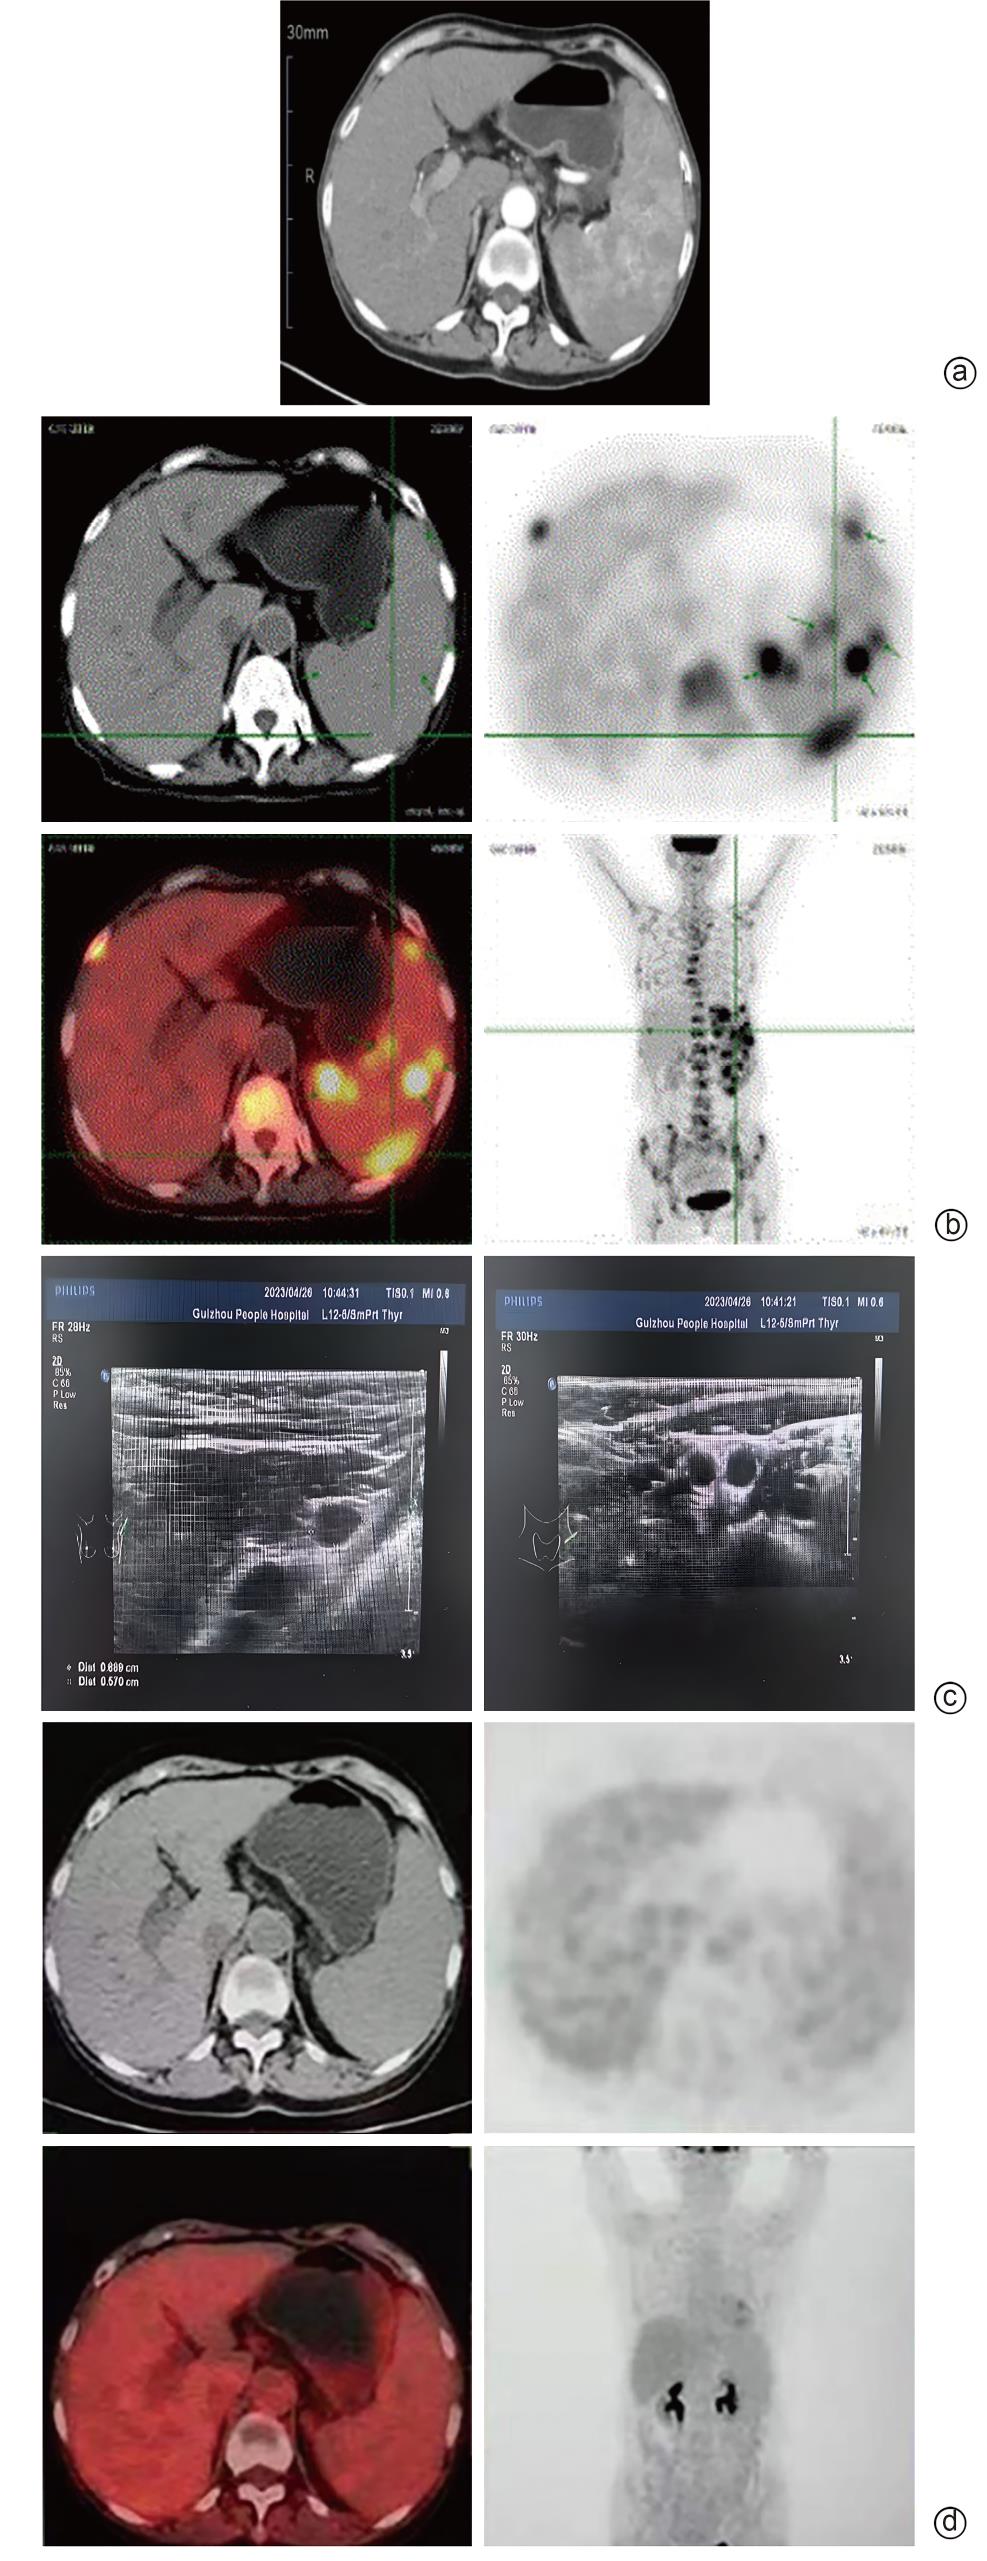

Primary splenic lymphoma misdiagnosed as Sjögren’s syndrome with liver cirrhosis: A case report

Chengcheng LI, Yuhong LIU, Lu WANG, Hong PENG, Xinhua LUO, Hong LI

2025, 41(9): 1883-1887. DOI: 10.12449/JCH250925

Abstract(437) HTML (101) PDF (5783KB)(60)

Abstract:

Primary splenic lymphoma is a rare malignant neoplasm, with similar clinical manifestations to Sjogren’s syndrome and liver cirrhosis, which often leads to misdiagnosis. This article reports a case of primary splenic lymphoma misdiagnosed as Sjogren’s syndrome with liver cirrhosis, in order to improve the understanding of primary splenic lymphoma, Sjogren’s syndrome, and liver cirrhosis and avoid misdiagnosis and treatment delay.